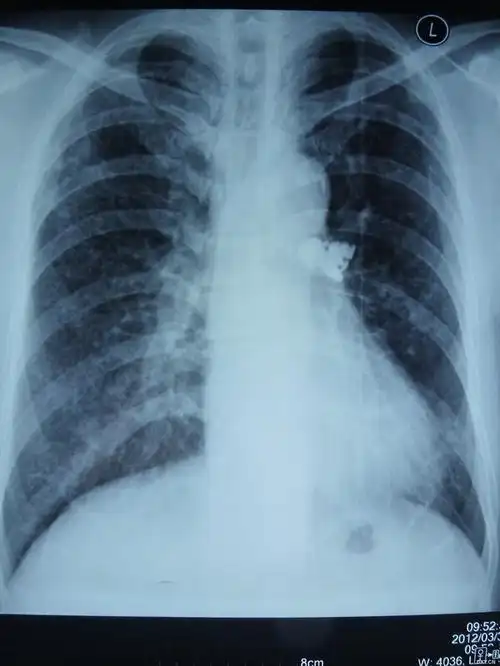

讨论胸部平片请讨论ct已经上传

【影像读片】一张正位胸片,看看考虑什么(结果已公布)

一张经典的胸片